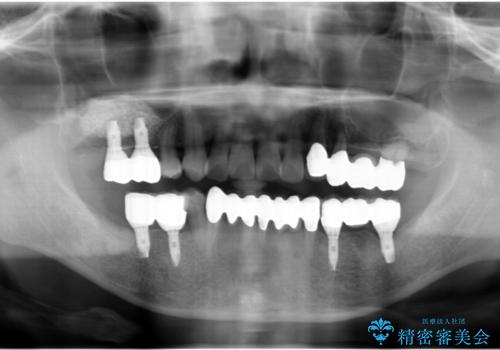

- 歯ブラシするたびに知覚過敏が辛く、改善を求めて来院されました。

過度なブラッシング圧により歯が削れてしまい、歯ぐきの下がりも認められます。

改善を図るため、結合組織移植を行い歯ぐきの再生を計画します。